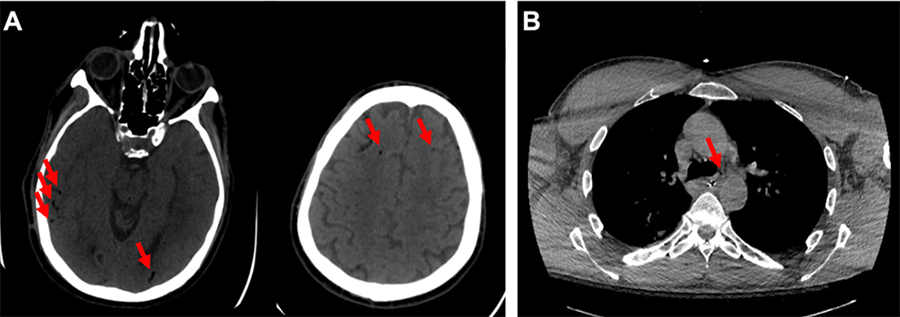

A 73-year-old male presented as a transfer from an outside hospital emergency room twenty days after percutaneous pulmonary vein isolation via radiofrequency ablation for symptomatic atrial fibrillation refractory to combination rate-controlling and anti-arrhythmic medication. He was found unresponsive at home with seizure-like activity and was brought to the emergency department, where computed tomography (CT) head revealed foci of air throughout bilateral cerebral hemispheres, and a CT chest revealed pneumomediastinum (Figure 1).

Figure 1. Imaging on Presentation. Published With Permission

A) CT head on initial presentation (arrows represent pneumocephalus); and B) CT chest on initial presentation (arrow represents pneumomediastinum).